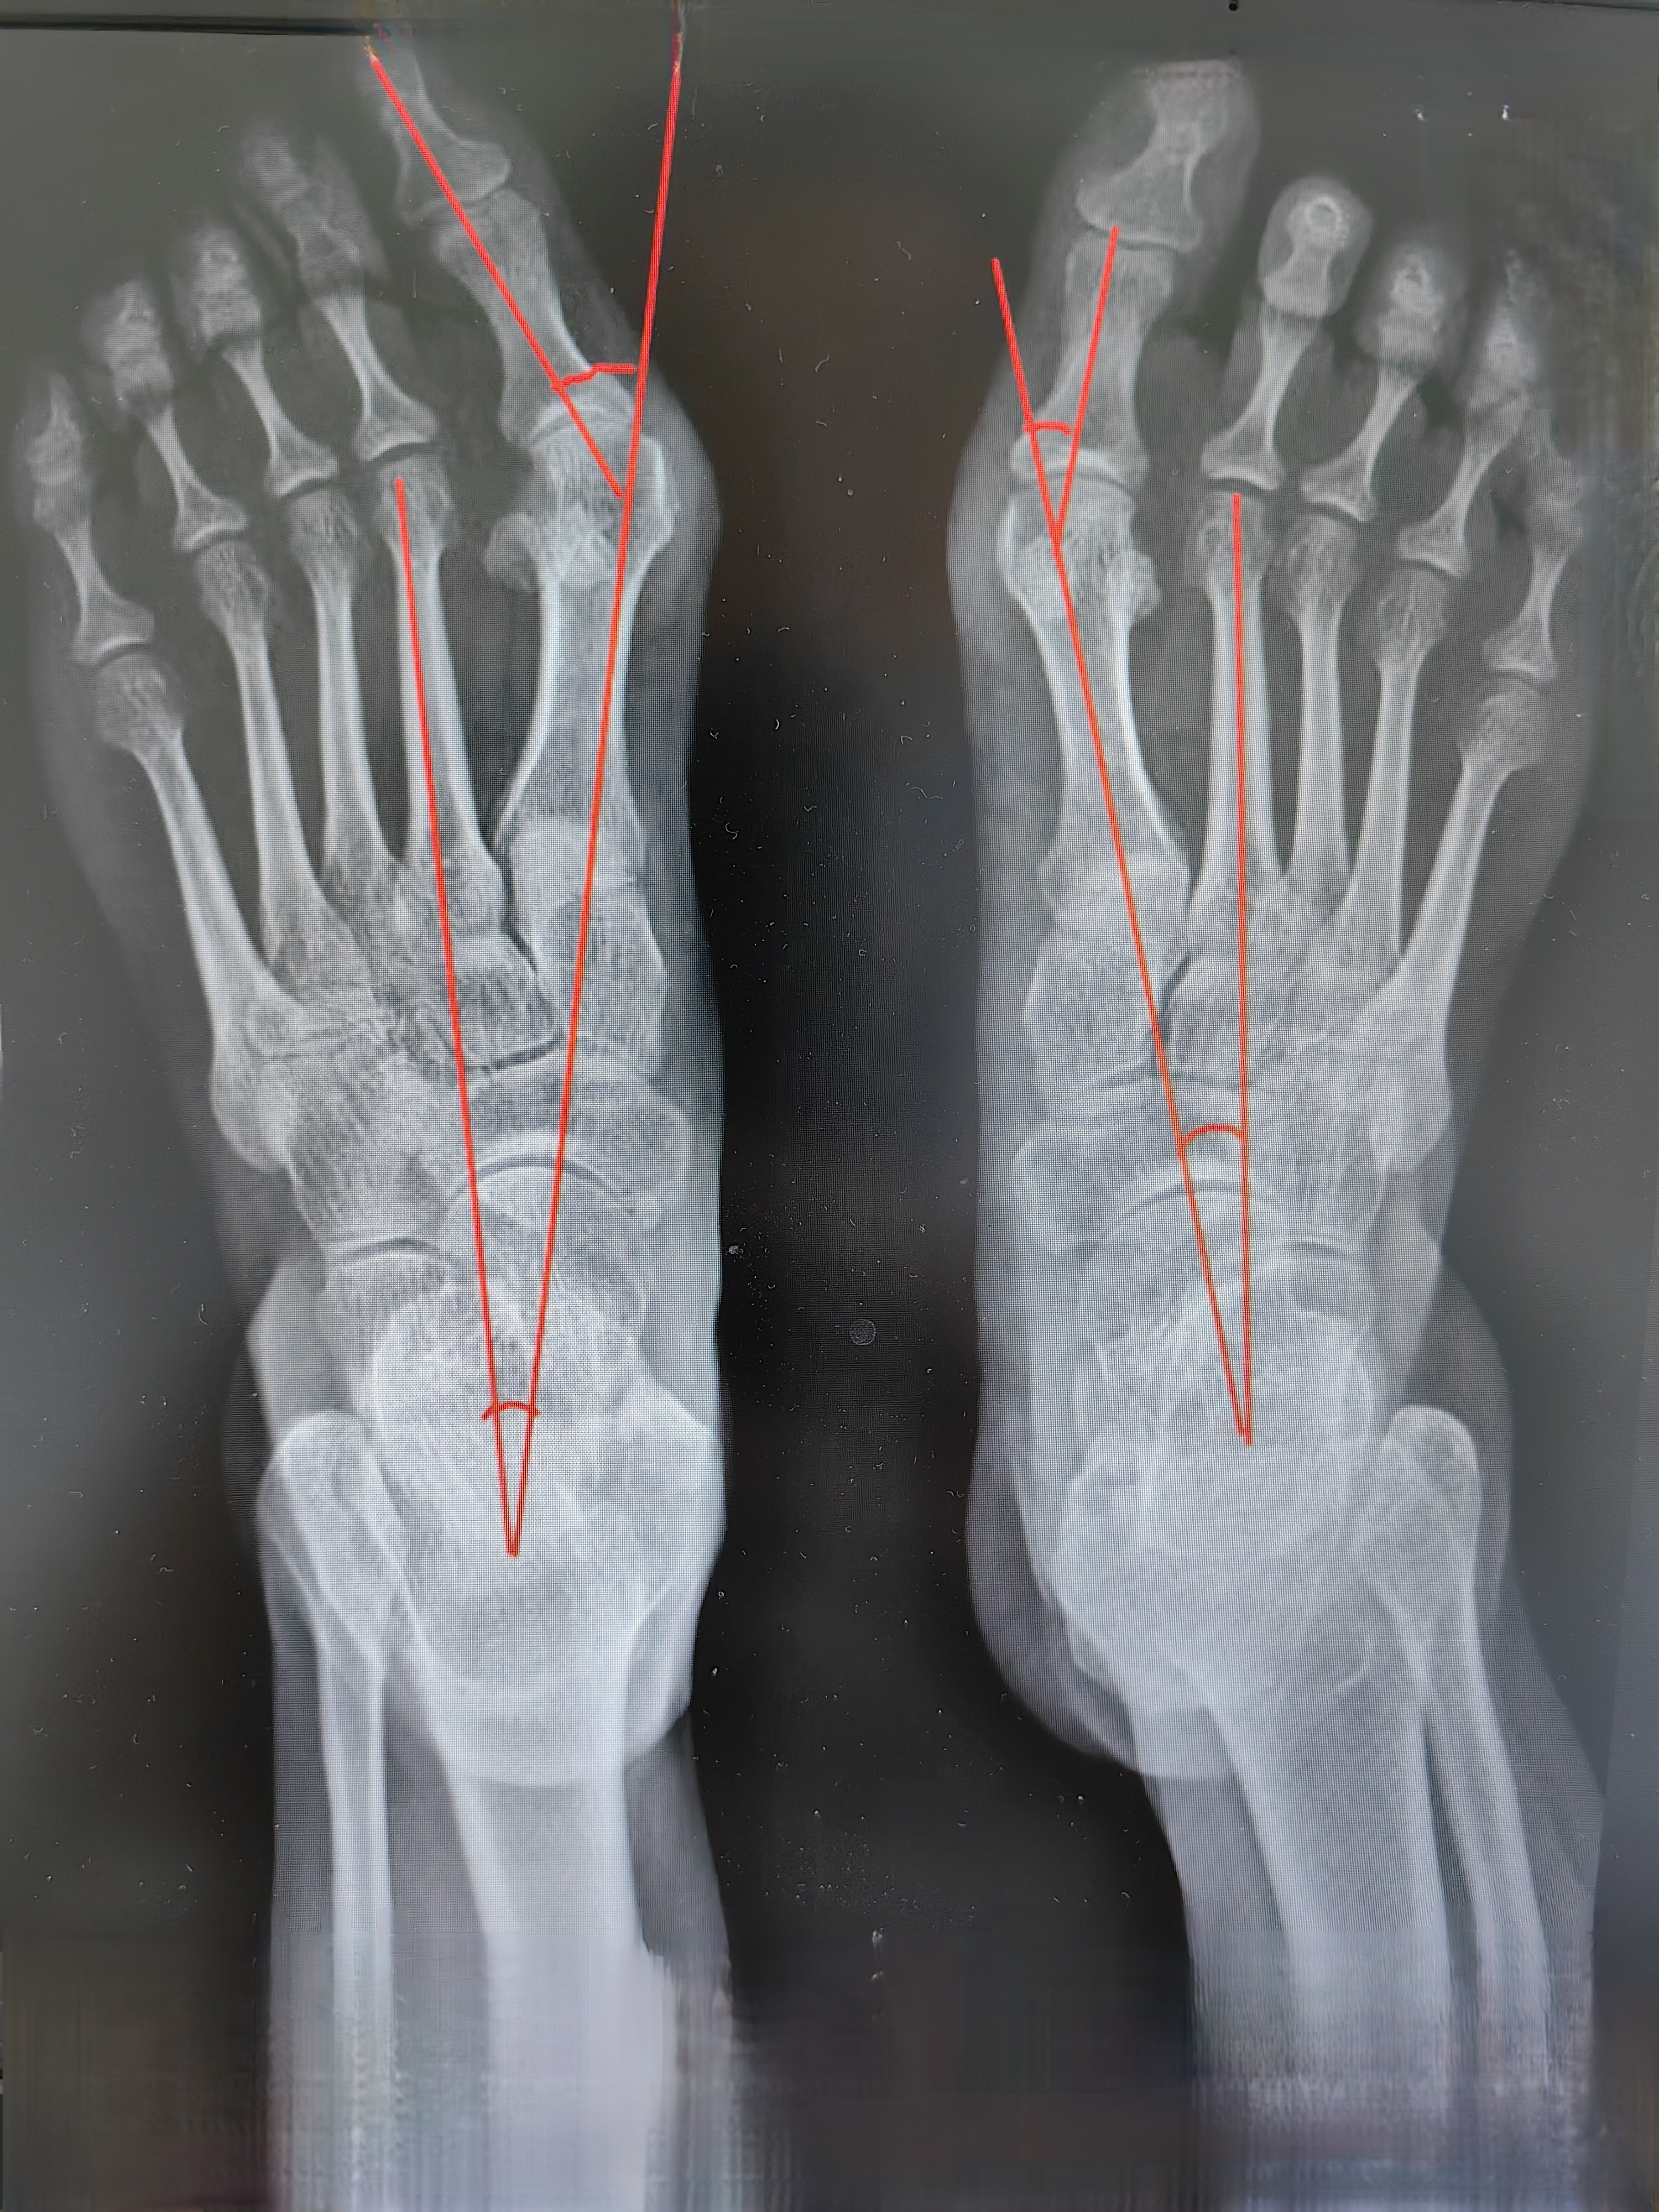

青少年拇外翻一般是指在11歲到19歲之間發(fā)生的拇外翻,約40%的成人拇外翻患者20歲以前就已發(fā)生拇外翻畸形。盡管青少年拇外翻手術治療的病例只占所有病例的10%以下,但青少年外翻的治療較成人更困難,具有較高的畸形復發(fā)率。本文聚焦青少年拇外翻的發(fā)病特點和治療方法,希望對此類患者有所幫助。(一)什么原因導致青少年拇外翻??目前認為,青少年拇外翻是多因素的作用,遺傳因素在本病的發(fā)生中占有更重要的作用。據報道,68%-80%的患者有家族遺傳史。?其他如穿鞋,第1跖骨頭的形態(tài),內側跖楔關節(jié)的傾斜和穩(wěn)定性和神經肌肉疾病等都可能對拇外翻的形成有影響。?(二)青少年拇外翻與成人拇外翻有什么不同??青少年拇外翻患者一般疼痛不是主要癥狀,多為影響穿鞋來就診。?拇趾內側的拇囊一般較小,外翻程度和跖骨內側骨贅都較小。?跖、趾骨的骨骺在年齡小的患者尚未閉合,約有一半的患者具有適合的跖趾關節(jié)。?對于第1跖趾關節(jié)不適合或半脫位的患者,畸形有進行性發(fā)展的可能。?部分患者伴有內側跖楔關節(jié)不穩(wěn)定、跟腱攣縮和其他足和下肢的畸形,如平足、短肢畸形、膝內外翻畸形等。?在青少年外翻患者中,跖趾關節(jié)骨性關節(jié)炎、跖骨頭軟骨損傷、跖間神經瘤很少見。?(三)青少年拇外翻的保守治療夾板、足墊和足部支具等可用于青少年外翻的非手術治療。但只能暫時減輕拇外翻癥狀,很難控制跟外翻的發(fā)展。因此,非手術治療適用于較小的兒童,等待骨骺閉合后手術治療。?(四)哪些需要手術治療?1.??????非手術治療失敗2.??????患者疼痛較重,影響穿鞋,畸形進行性加重。3.??????合并平足癥、足趾畸形,如錘狀趾、騎跨趾的出現,需要手術治療。4.??????對于手術時機的選擇仍有不同意見。有些醫(yī)生認為手術可能會影響骨骺發(fā)育,應等到骨骺閉合后再進行。而另一些醫(yī)生認為,畸形的進行性發(fā)展可能對跖趾關節(jié)產生永久的影響,應早期糾正。?(五)青少年拇外翻的分型:Pontious將青少年外翻分為兩型1.??????I型患者畸形出現的早,有家族遺傳史,畸形明顯,可伴有其他畸形,如足下垂、足外翻等加重拇外翻畸形的力量,應早期手術治療。2.??????Ⅱ型患者畸形不重,發(fā)展慢,可以予以觀察或非手術治療。??拇外翻測量最重要的三個角:??正常:拇外翻角HVA<20°,第1、2跖間角IMA<9°,跖骨遠端固定角DMAA<7.5°??輕度:20度

40度以上;IMA>16度以上,以上數據只要達到一項,即可定位該類型(六)手術方式有哪些?1.遠端軟組織手術:單純軟組織手術對于糾正青少年跗外翻作用有限,一般需要合并其他手術共同使用。2.第1跖骨遠端截骨術:絕大部分用于成人拇外翻治療的第1跖骨遠端截骨術也都適合用于青少年。?3.第1跖骨近端截骨術:成人采用第1跖骨近端截骨術的適應證一般為IMA(第1、2跖骨間角)>15°。對于青少年拇外翻來說,畸形可能將來進一步發(fā)展,可早期采用第1跖骨近端截骨術將IMA縮小到0°甚至輕度負角。因此,IMA<15°時也可行此類手術。4.跖骨-楔骨手術:由于一些醫(yī)生認為第1跖骨內翻是引起外翻畸形的主要原因。對于嚴重的第1跖骨內翻和內側跖楔關節(jié)過度內側傾斜的青少年外翻,采用內側楔骨開放性截骨。一般需要同時行跖骨遠端截骨,以進一步糾正畸形。5.骨骺閉合術在兒童外翻,可以使用騎縫釘固定阻滯第1跖骨基底外側骨骺生長的方法達到糾正第1跖骨內翻的目的。取出騎縫釘恢復骨骺生長。同時結合跖骨遠端截骨術和軟組織手術。6.近節(jié)趾骨截骨術:糾正拇趾的外翻畸形以達到更好的矯正效果。(七)小結1.青少年拇外翻常合并松弛性扁平足,術后容易復發(fā);2.常合并趾間關節(jié)外翻;3.拇外翻家族史;4.需2或3個部位聯合截骨;5.15歲前手術效佳;6.影響足部美觀,合并陽性家族史可作為手術指征;7.青少年在發(fā)育期,術后有一定的復發(fā)幾率;8.跖骨遠端關節(jié)固定角增大是青少年拇外翻的重要特征;9.跖楔關節(jié)異常傾斜致第一跖骨內翻是青少年拇外翻的一個主要致畸因素;10.手術注意保護骨骺。?(八)病例示例? 陳超醫(yī)生的科普號2025年02月26日139